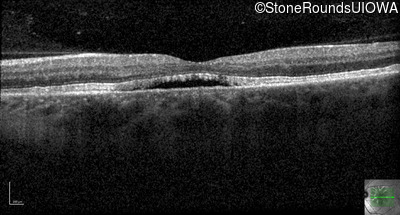

Age at visit: 49 years

This 49 year old man first experienced some mild metamorphopsia at age 35.

Age at visit: 51 years

Age at visit: 52 years